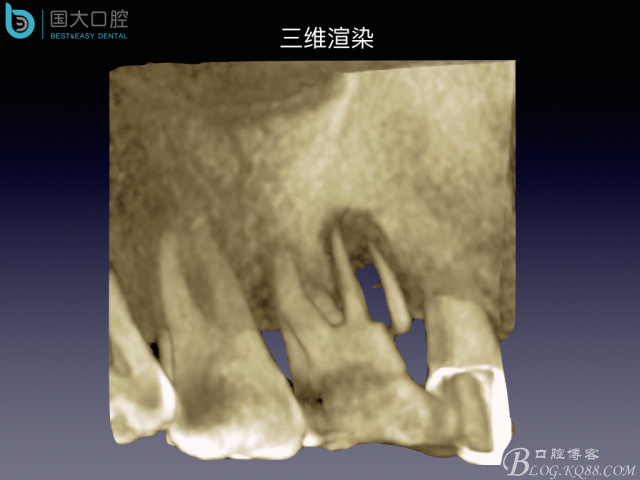

嚴(yán)重根尖周炎能做即刻種植嗎?